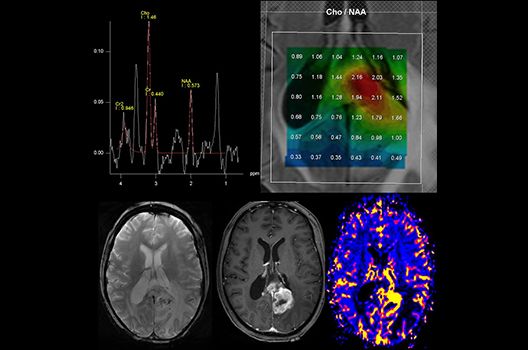

- MR-Protonenspektroskopie

Die Magnetresonanztomographie (MRT) ist ein Verfahren, bei dem durch magnetische Kräfte Bilder des Körperinneren angefertigt werden. In der Neuroradiologie können manchmal kleinste Veränderungen schwere Folgen haben; daher forschen wir an der Entwicklung hochauflösender MRT-Sequenzen, mit denen diese Prozesse und auch einzelne Nervenfaserbahnen sichtbar gemacht werden können. Darüber hinaus sind bei vielen Erkrankungen des Gehirns die Blutgefäße betroffen. Daher arbeiten wir an der Neu- und Weiterentwicklung von MRT-Sequenzen zur Darstellung der Blutgefäße und zur Blutflussanalyse (sog. „Angio-MRT“). Einen besonderen Forschungsschwerpunkt unserer Klinik stellen die MR-Protonenspektroskopie und die funktionelle MRT dar, mit denen die Analyse einzelner chemischer Substanzen im Hirngewebe oder die Darstellung ausgewählter Hirnfunktionen möglich ist.

Die Hybridbildgebung mittels PET/MRT spielt insbesondere in der onkologischen Bildgebung eine wichtige Rolle. Eine mögliche Fragestellung ist die Unterscheidung zwischen einem Tumorrezidiv oder therapeutisch assoziierten Veränderungen insbesondere dann, wenn diese Frage mittels MRT alleine nicht beantwortet werden kann.

Die bildgebende Diagnostik und Verlaufsbeurteilung von Tumoren des Nervensystems ist einer der klinischen und Forschungsschwerpunkte unserer Abteilung. Eine besondere Bedeutung kommt der Hybrid-Bildgebung zu. Das Universitätsklinikum verfügt über einen integrierten Ganzkörper-PET/MRT-Scanner, der die Vorteile der MRT-Bildgebung und der Positronenemissionstherapie (PET) vereinigt. Aufgrund der langjährigen klinischen Arbeit und Forschungstätigkeit mit diesem Gerät hat die Neuroradiologie Tübingen maßgeblich zur Etablierung dieses Verfahrens beigetragen. Auch weiterhin forschen wir intensiv an neuen Methoden zur frühen Einordnung von Tumoren und insbesondere Tumorrezidiven, die mit anderen Methoden häufig nicht erfasst werden können.